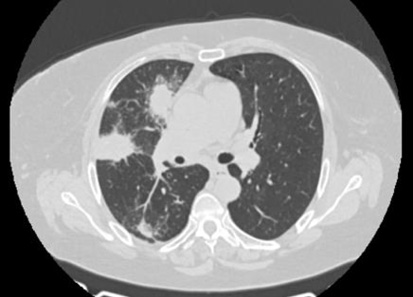

Por mejoría del cuadro clínico, se programó TC de tórax control al mes en la que se visualizaron dos imágenes nodulares a nivel de lóbulo superior derecho. (Figura 2) La punción percutánea con aguja fina de la lesión consolidativa nodular concluyó en la ausencia de atipias en la anatomía patológica, pero con marcadores tumorales TTF1, CK 7 y P63 positivos. Una nueva TC de tórax mostró franca mejoría de las imágenes nodulares previamente descritas, pero con la aparición de un nódulo de 15 mm en lóbulo inferior izquierdo. (Figura 3) Posteriormente, se decidió realizar biopsia quirúrgica por medio de una videotoracoscopía (VATS) de la lesión de la base pulmonar izquierda y la anatomía patológica informó un patrón inflamatorio inespecífico (ver exámenes complementarios).

Imágenes nodulares a nivel de lóbulo superior derecho.